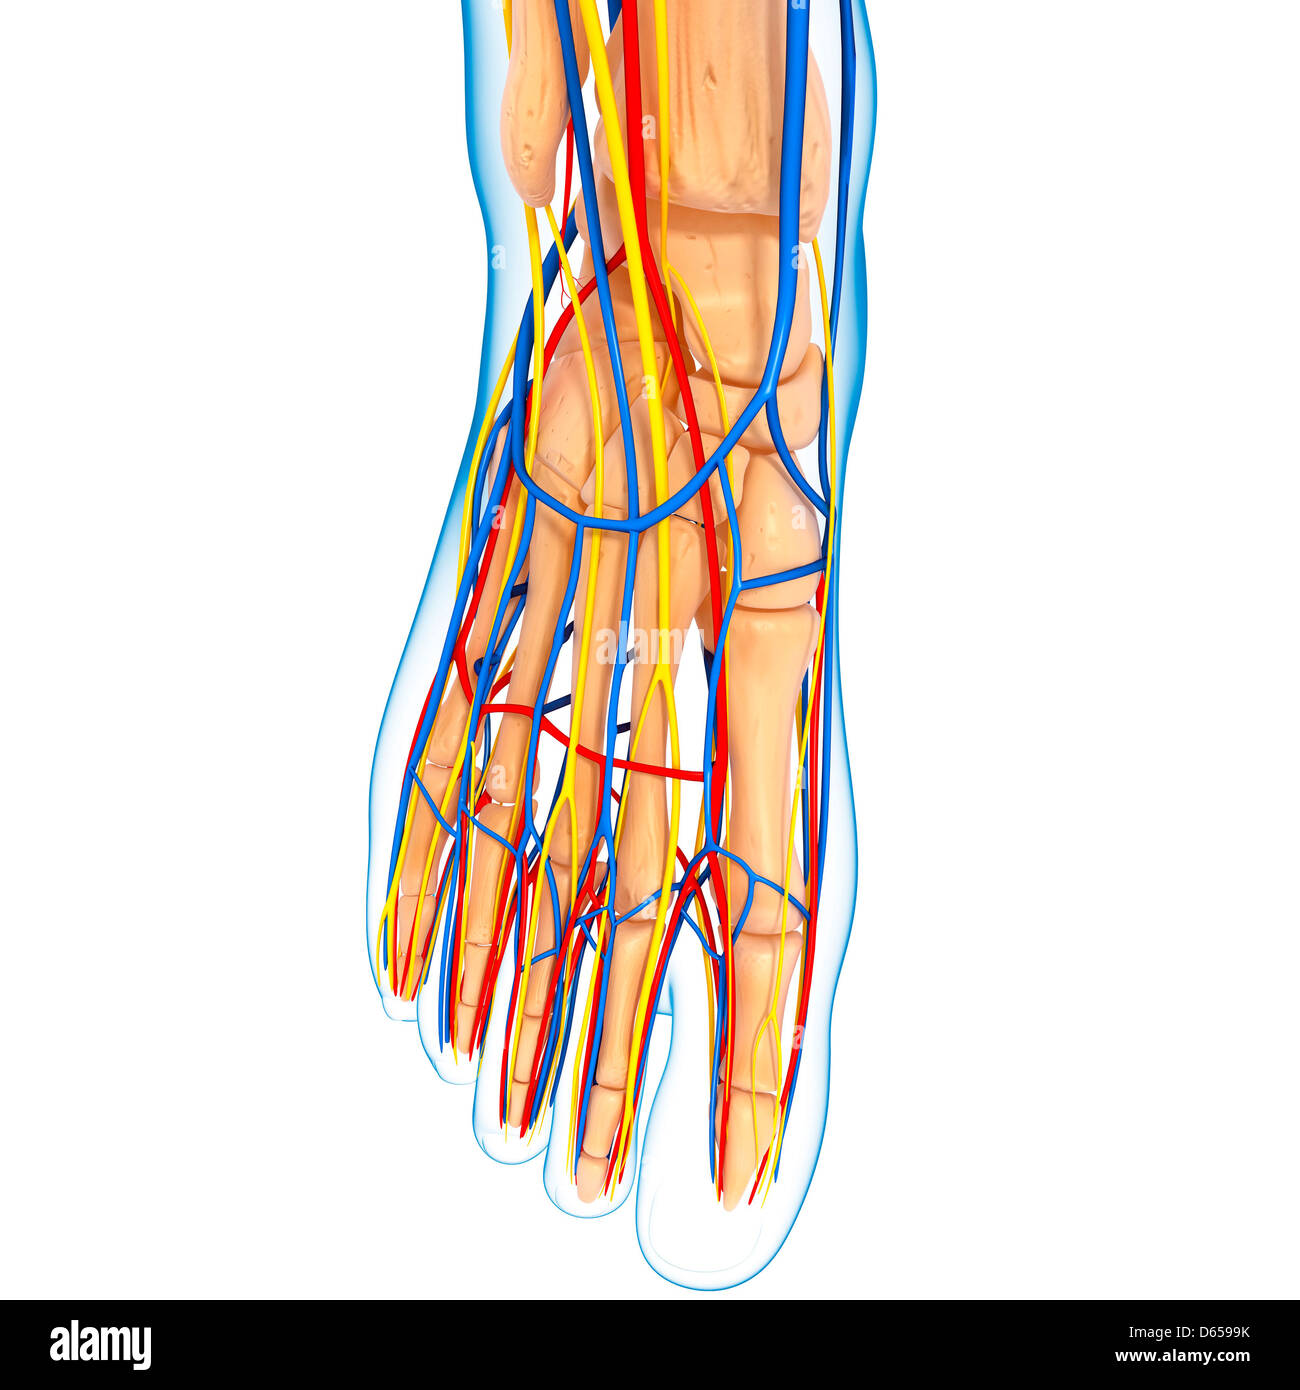

RF2ABM669–La médecine et les soins de l'illustre le tableau, les droits de l'anatomie du pied : Peau et tissus ectodermaux, os, muscles nerfs, vaisseaux sanguins